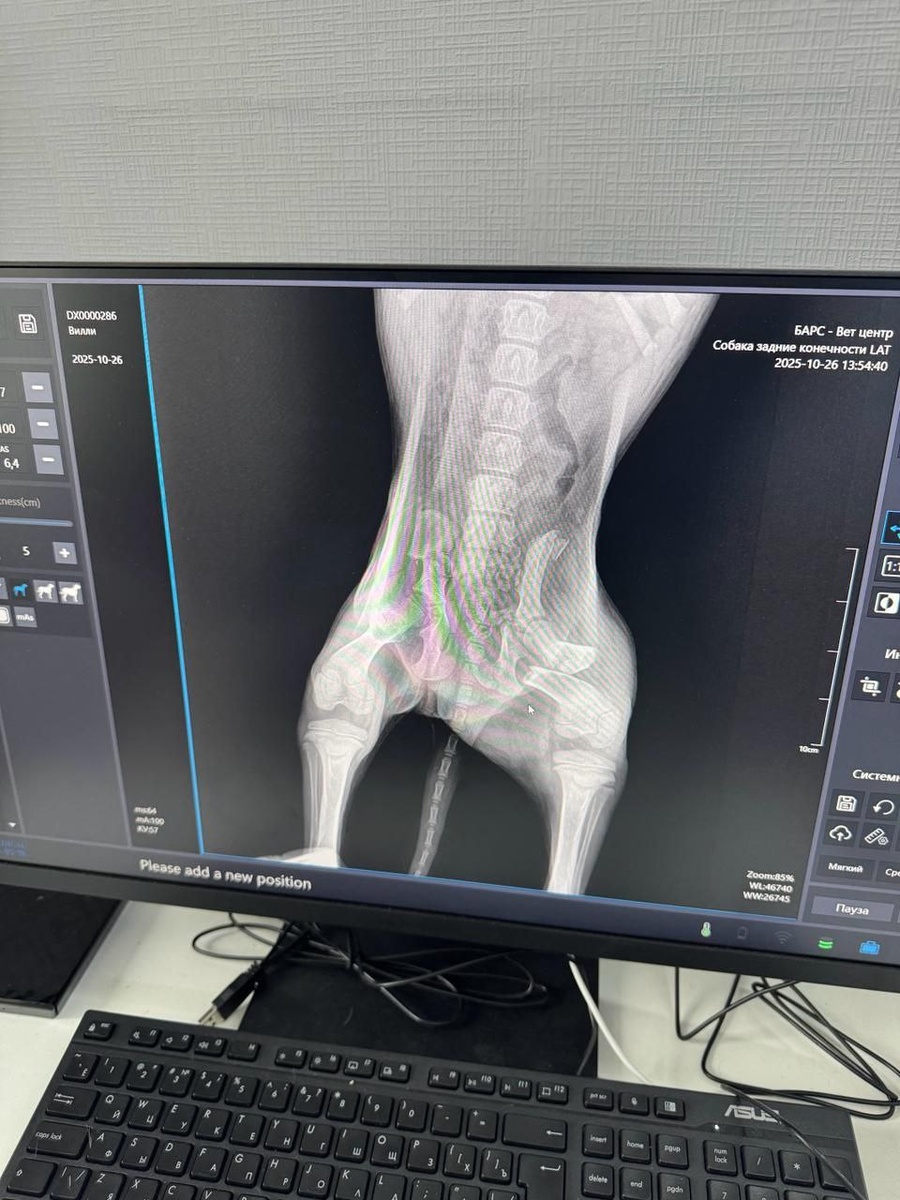

Рентген показал несколько переломов.

После ДТП несколько переломов, завтра будет операция ❗